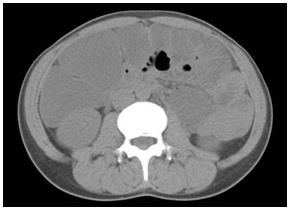

照片2:普通CT 照片

腹部全體發(fā)白。由于1.5L腸道準(zhǔn)備藥物停滯腸內(nèi),無(wú)法看見(jiàn)肝下緣,腎陰影,腸腰筋。看似腹水。橫結(jié)腸中有少量氣體。盆腔正中存在硬便和裂縫狀氣體。

照片3:腹部CT 照片,軸向圖像,上腹部

腸道內(nèi)堆積腸道準(zhǔn)備藥物明顯。腎臟前為升結(jié)腸,當(dāng)中是橫結(jié)腸。